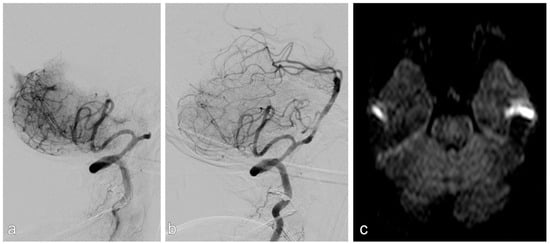

In ELVO cases (example given in Figure 3), mechanical thrombectomy was always performed first using either a non-detachable stent retriever and/or an aspiration catheter. If the angiographic result was insufficient, including persistent occlusion, re-occlusion attributable to an underlying stenosis, or a residual high-grade stenosis, rescue treatment with a self-expanding stent (Solitaire AB, Medtronic, Minneapolis, MN, USA) was performed. If necessary, stenoses were dilated pre and/or after stent placement with an undersized balloon. In some cases, balloon-expandable stents were used for this indication, if feasible.

Figure 3. Patient with acute stroke due to acute occlusion of the basilar artery (a). After mechanical thrombectomy, there was a high-grade stenosis, which was stented successfully (b). There was no infarction on MRI upon discharge (c).

Successful reperfusion (mTICI ≥ 2b) was achieved in 94% of ELVO patients (Figure 3).